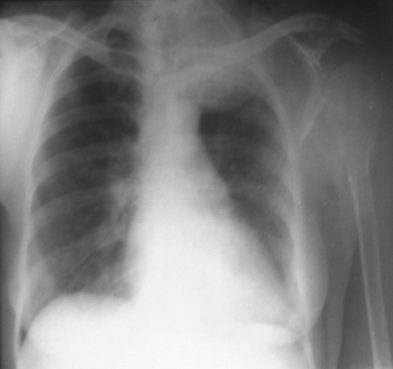

Rx toracică, incidență P-A

DESCRIERE:

la niv. întregului hemitorace drept → opacitate extinsă, nesistematizată, de intensitate mare, omogenă

caracter expansiv → împinge traheea și mediastinul de partea opusă

diafragm deplasat în jos

lărgirea spațiilor intercostale

umplerea spațiului costo-diafragmatic

DX: pleurezie masivă

DD: atelectazie → caracter retractil